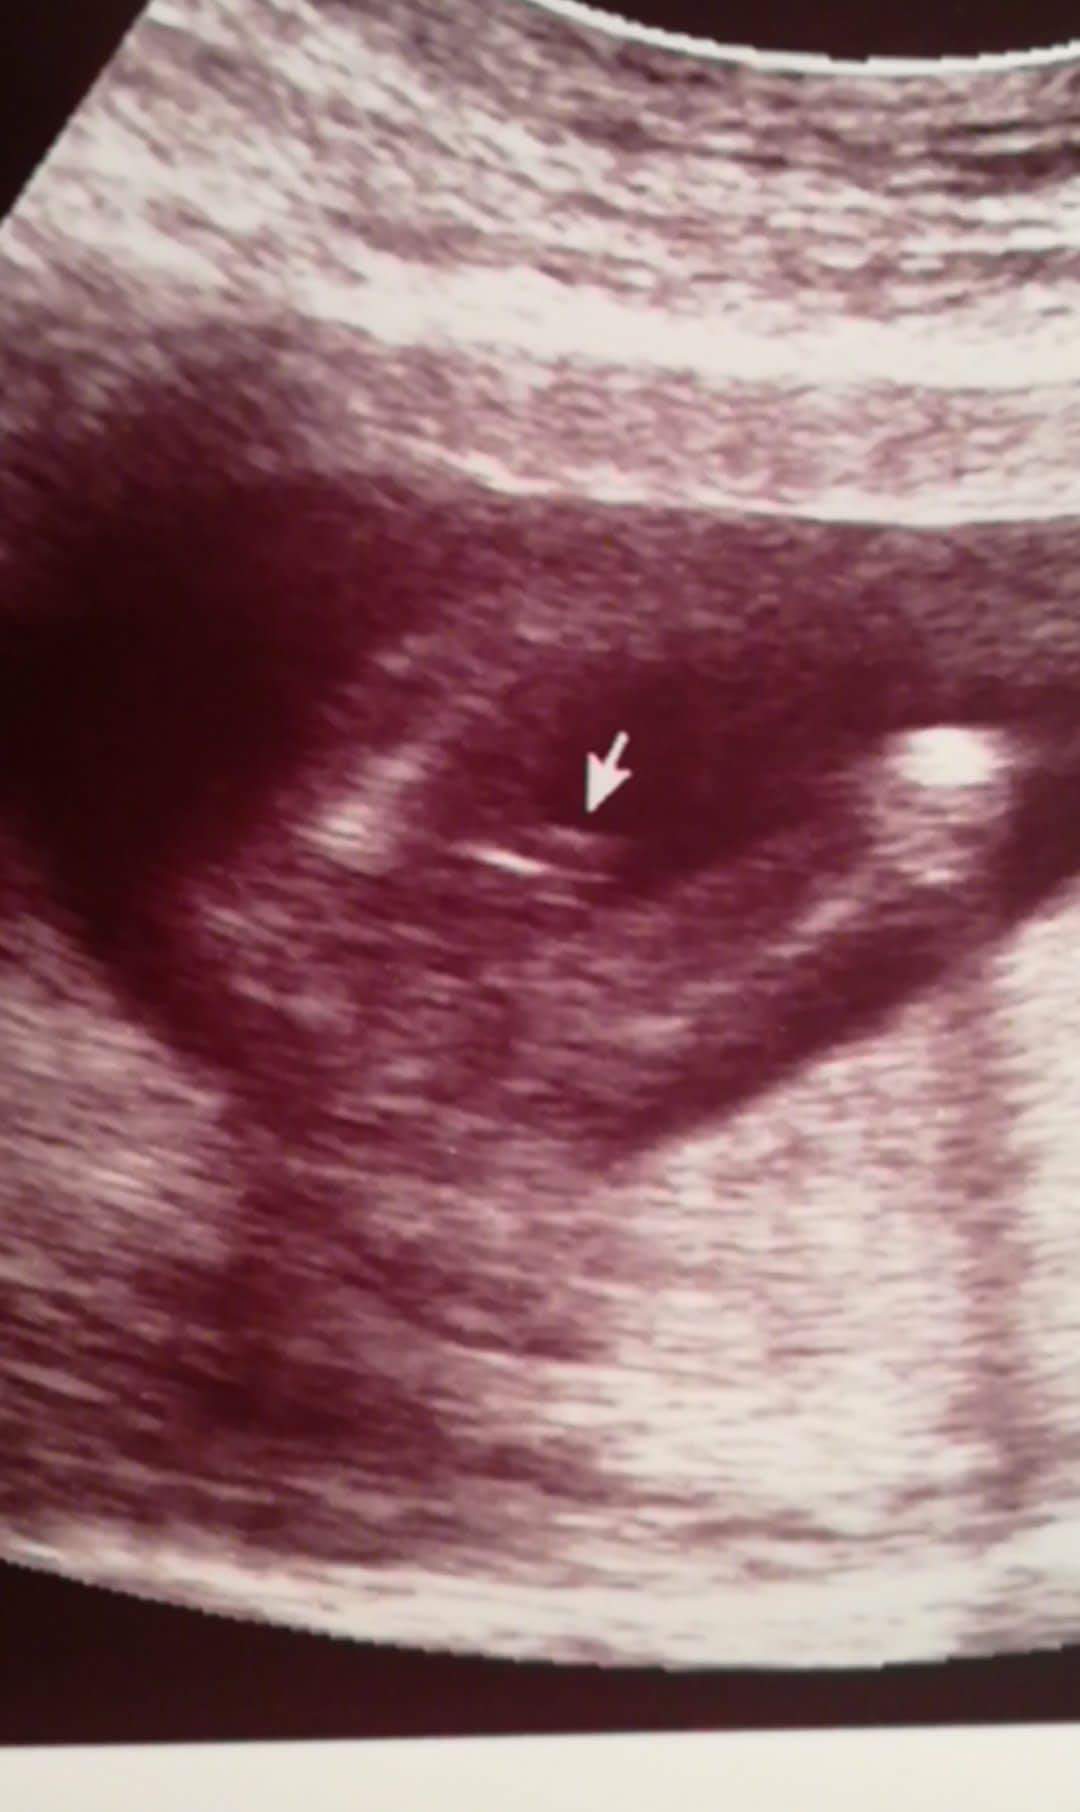

Witam w 19 tygodniu ciąży dowiedziałam się ze będę miała dziewczynkę w 20 tyg okazało się jednak , że to chłopak. Sama już nie wiem bo na jednym usg widać na pewno dziewuche a na drugim chłopca. Może to pempowina ?? Może ktoś mi pomoże rozwiązać ta zagadkę

• 4A8F5FF1-76CA-4DE0-AC12-5EDF08E820F2.jpg

4A8F5FF1-76CA-4DE0-AC12-5EDF08E820F2.jpg

596,4 KB · Wyświetleń: 44 068